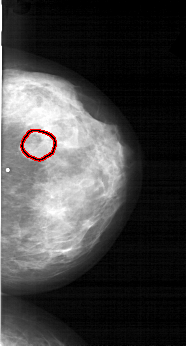

A_1566_1.LEFT_MLO

LEFT_MLO LINES 6346 PIXELS_PER_LINE 3751 BITS_PER_PIXEL 12 RESOLUTION 43.5 NON_OVERLAY

FILE: A_1566_1.RIGHT_MLO.OVERLAY

TOTAL_ABNORMALITIES 1

ABNORMALITY 1

LESION_TYPE MASS SHAPE LOBULATED MARGINS OBSCURED

ASSESSMENT 4

SUBTLETY 3

PATHOLOGY BENIGN

TOTAL_OUTLINES 1

BOUNDARY